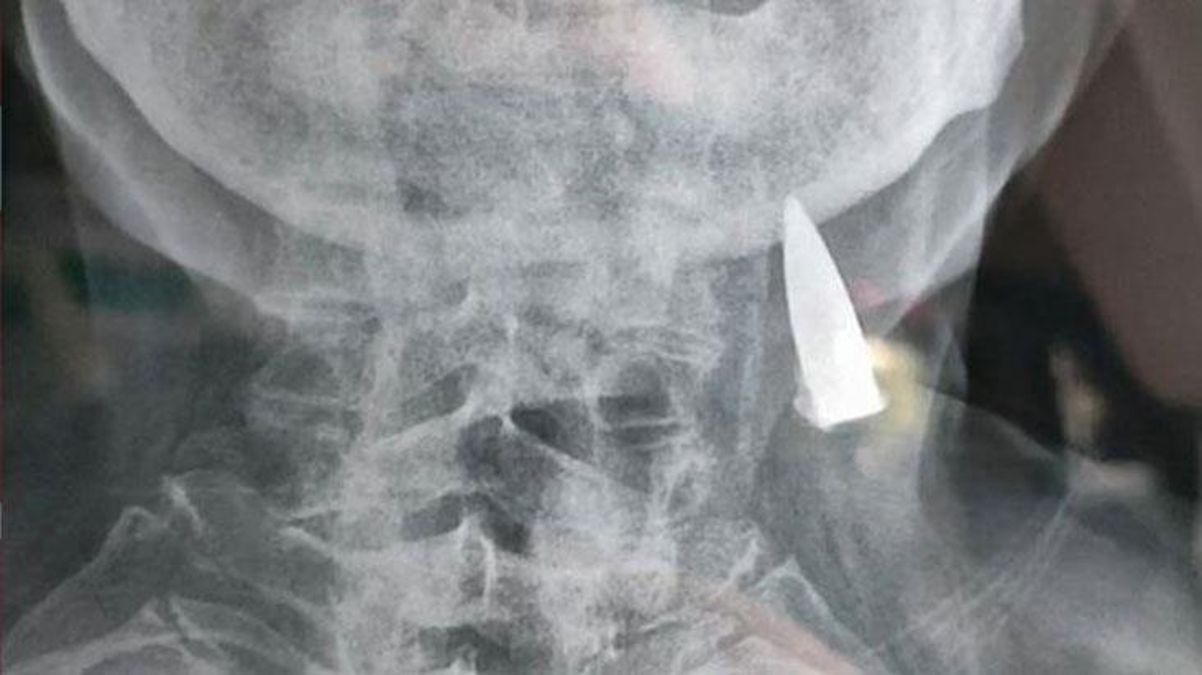

İkinci Dünya Müharibəsində iştirak edən 95 yaşlı Zhao He baş ağrısı şikayəti ilə getdiyi xəstəxanada rentgen çəkdirib. Xəstənin rentgenini yoxlayan həkimlər gördüklərindən dəhşətə gəliblər.

KONKRET.az “haberler.com” saytına istinadən xəbər verir ki, həkimlər xəstənin boğaz nahiyəsində mərmi olduğunu müəyyən ediblər.

Mövzu ilə bağlı açıqlama verən Zhaonun kürəkəni bildirib ki, qayınatası müharibə zamanı çoxlu güllə yarası alıb, lakin o, bundan xəbərsiz olub. 95 yaşlı qoca yaşının çox olması səbəbindən riskli hesab edilən əməliyyatı qəbul etməyib və 70 ildir daşıdığı mərminin çıxarılmasını istəməyib.